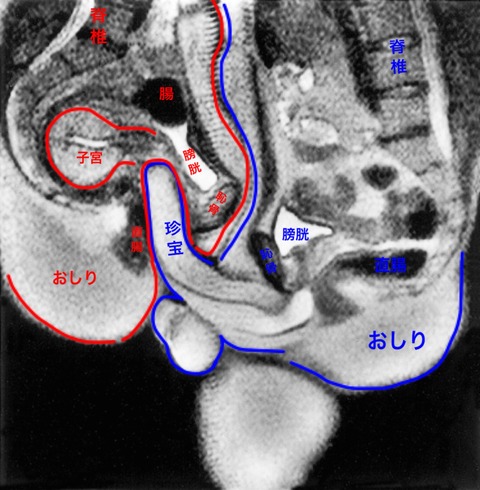

珍宝

俺のちんぽじゃ到底子宮に届かないんだけど?

>>4

ちんぽじゃねぇ珍宝だ

ちんぽじゃねぇ珍宝だ